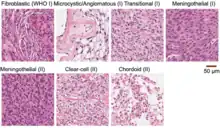

Although the majority of meningiomas are benign, they may have malignant presentations. Classification of meningiomas are based upon the WHO classification system.[23]

- Benign (Grade I) – (90%) – meningothelial, fibrous, transitional, psammomatous, angioblastic

- Atypical (Grade II) – (7%) – chordoid, clear cell, atypical (includes brain invasion)

- Anaplastic/malignant (Grade III) – (2%) – papillary, rhabdoid, anaplastic (most aggressive)

The modern term of "meningioma" was used first by Harvey Cushing (1869–1939) in 1922, to describe a set of tumors that occur throughout the neuraxis (brain and spinal cord), but have various commonalities.[40][41] Charles Oberling then separated these into subtypes based on cell structure and, over the years, several other researchers have defined dozens of different subtypes as well. In 1979, the World Health Organization (WHO) classified seven subtypes, upgraded in 2000 to a classification system with nine low-grade variants (grade I tumors) and three variants each of grade II and grade III meningiomas.[41] The most common subtypes are Meningotheliomatous (63%), transitional or mixed-type (19%), fibrous (13%), and psammomatous (2%).[7]